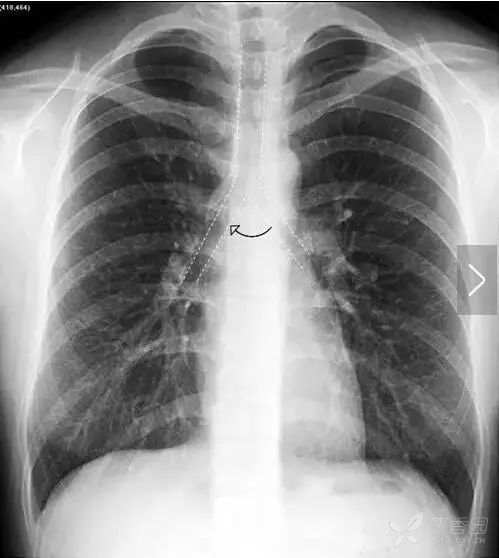

在解剖结构上,肺叶由叶间裂胸膜自然分隔而成,左肺由斜裂分为上、下2个叶,右肺由水平裂(横裂)和斜裂分上、中、下3个叶。胸部X线平片中,叶间裂胸膜和X线方向平行时可以显影,呈细线状。其中,正位胸片常可以看到右肺水平裂(图11)。

图11 右肺水平裂。正位胸片常可以看到细线状的右肺水平裂,位于右肺野中部,自肺野边缘向右肺门水平走行,水平裂以上为右肺上叶,以下为右肺中叶和下叶。

正位胸片上无法看到两肺斜裂。侧位胸片常可见两肺的斜裂(图12)。侧位片也可见水平裂(图12),起自斜裂中点附近,向前水平或稍向下达前胸壁。